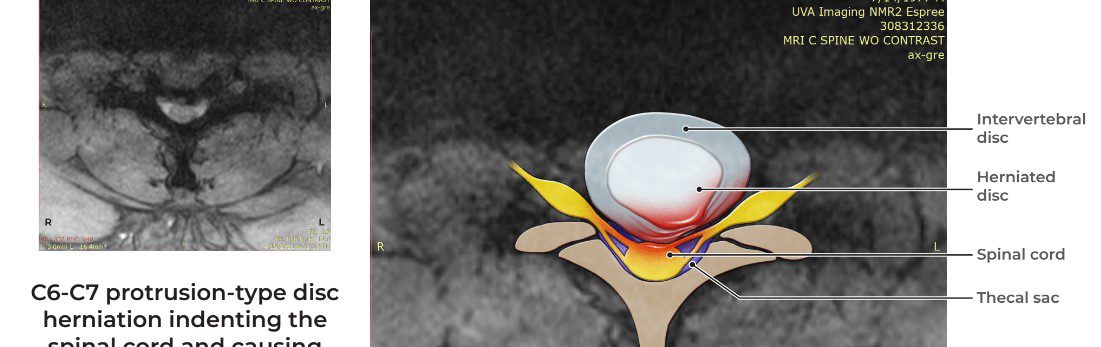

One of the challenges in this case, besides the very likeable defendant, was that in the decade before the crash, the client consistently and repeatedly complained about neck pain and associated radicular symptoms stemming from two earlier car crashes. He had consistent treatment for his neck problems during this time and even had two prior neck surgical consultations. While his prospective surgeons noted that he had moderate to severe central stenosis at his C6-C7 levels before this collision, they declined to operate because Plaintiff did not have myelopathy, or impingement of the spinal cord. As a result, the prospective surgeons advised against C6-C7 surgery even though Plaintiff found his neck condition to be potentially disabling.

Two months after the collision, Mr. Byrne’s client visited the emergency department complaining of difficulty walking. Emergency room physicians determined that his condition had progressed and that he now suffered from myelopathy. Physicians determined it was necessary to perform an emergency ACDF surgery at the C6-C7 level. The surgery was performed.

The biggest hurdle in the case dealt with differentiating the client’s moderate-to-severe central stenosis that existed before the collision from the severe central stenosis and myelopathy that arose after the collision. Mr. Byrne came to Focus Graphics to create a number of illustrations that compared the client’s before and after MRI imaging. Focus Graphics helped highlight the subtle differences in the MRI imaging, and their illustrations helped the medical experts explain how those subtle visual differences had dramatic functional consequences for the client. Focus Graphics also provided helpful illustrations showing his shoulder injuries and the ACDF procedure that was completed.